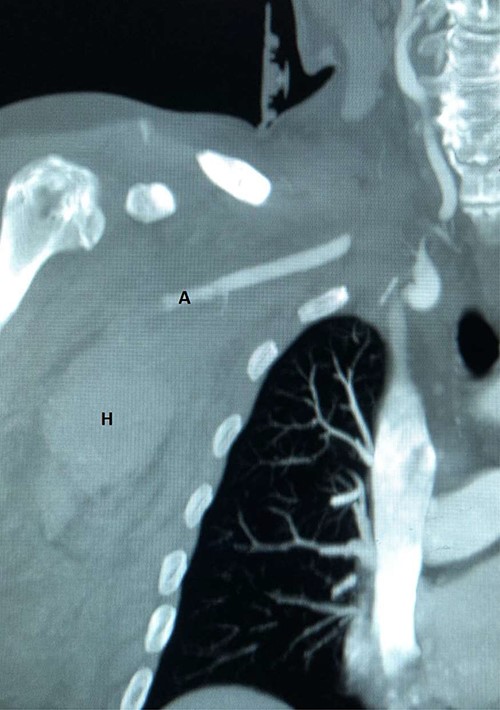

Plain radiographs of the right humerus and shoulder did not show any fracture or dislocation. A computed tomography (CT) scan with arterial phase angiography did not show and acute fracture of the cervical spine, but did reveal an abrupt cessation in flow in the right axillary artery secondary to traumatic occlusion of the vessel at the junction of segment 2 going into segment 3 with significant surrounding haematoma (Figs. 1 and 2).

CT angiography reconstructed views demonstrating absent flow beyond segment 1 of the right axillary artery (A) with haematoma in the right axilla (H).